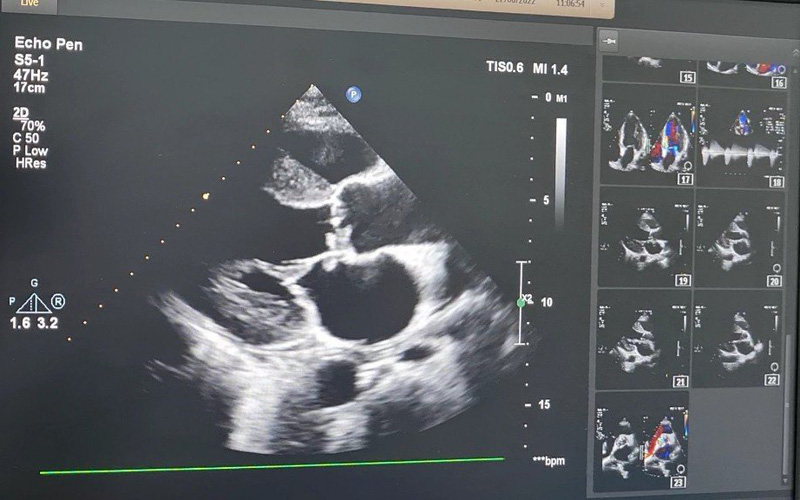

Siêu âm tim anh T. phát hiện cục sùi lớn, gây thủng van và làm hở nặng van hai lá. Ảnh: BVCC